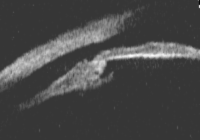

睫状体在手术或外伤的情况下,可能发生房角后退、睫状体截离(图1、表1)、睫状体疤痕或前膜(前部PVR)、睫状体脱离(图2)/脉络膜脱离、睫状体水肿、睫状体缺损等并发症,影响睫状体的正常功能,使房水分泌减少,眼压降低。

图2. 睫状体脱离:睫状体与巩膜之间分离,睫状肌纵行纤维仍附着于巩膜突上